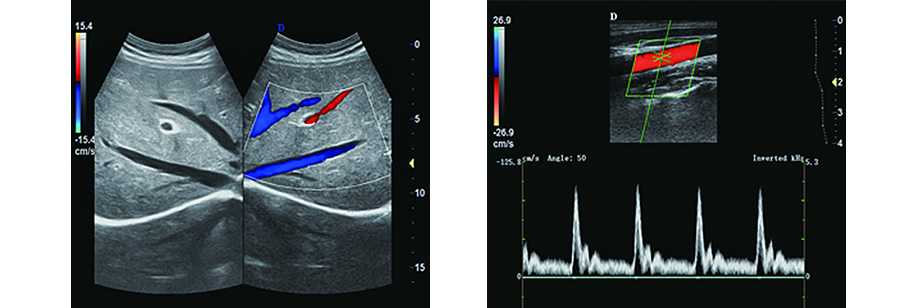

1.心臟和CW:提供成人及兒童相控陣探頭用于心臟檢查。獨立的連續波形成提供高信噪比圖象

2.血管應用:多種高頻探頭可用于血管檢查,支持彩色和PW、三同步、聲束偏轉、角度校正、2D/彩色同步顯示以及方便快捷的測量和報告